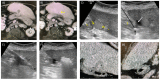

Percutaneous ablation is an accepted treatment modality for primary hepatocellular carcinoma (HCC) and liver metastases. The goal of curative ablation is to cause the necrosis of all tumour cells with an adequate margin, akin to surgical resection, while minimising local damage to non-target tissue. Aside from the ablative modality, the proceduralist must decide the most appropriate imaging modality for visualising the tumour and monitoring the ablation zone. The proceduralist may also employ protective measures to minimise injury to non-target organs. This review article discusses the important considerations an interventionalist needs to consider when performing the percutaneous ablation of liver tumours. It covers the different ablative modalities, image guidance, and protective techniques, with an emphasis on new and advanced ablative modalities and adjunctive techniques to optimise results and achieve satisfactory ablation margins.